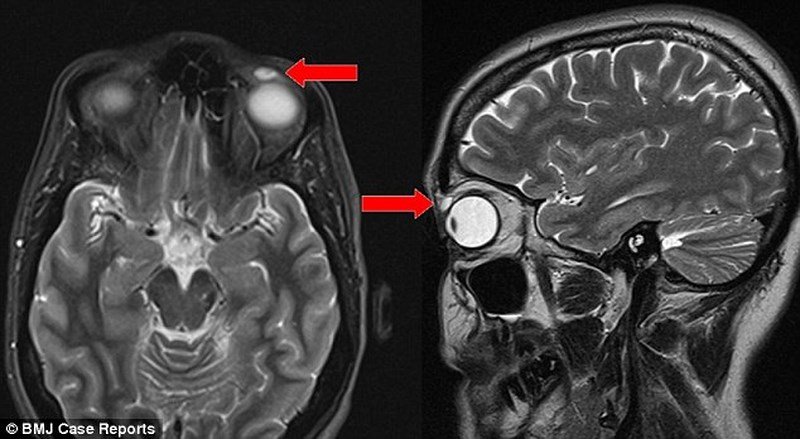

Nhưng sau khi ca tiểu phẫu hoàn thành, họ mới phát hiện cục u đó thực chất là chiếc áp tròng dính vào mí mắt bệnh nhân cách đây 28 năm.

Các bác sỹ hiện vẫn chưa thế giải thích lý do vì sao kính áp tròng yên vị tại đó gần 30 năm mà không gây cộm hay viêm mà chỉ mới rạn nứt cách đây nửa năm khiến người phụ nữ khó chịu.

Chiếc kính áp tròng được lấy ra khỏi mí mắt sau 28 năm.